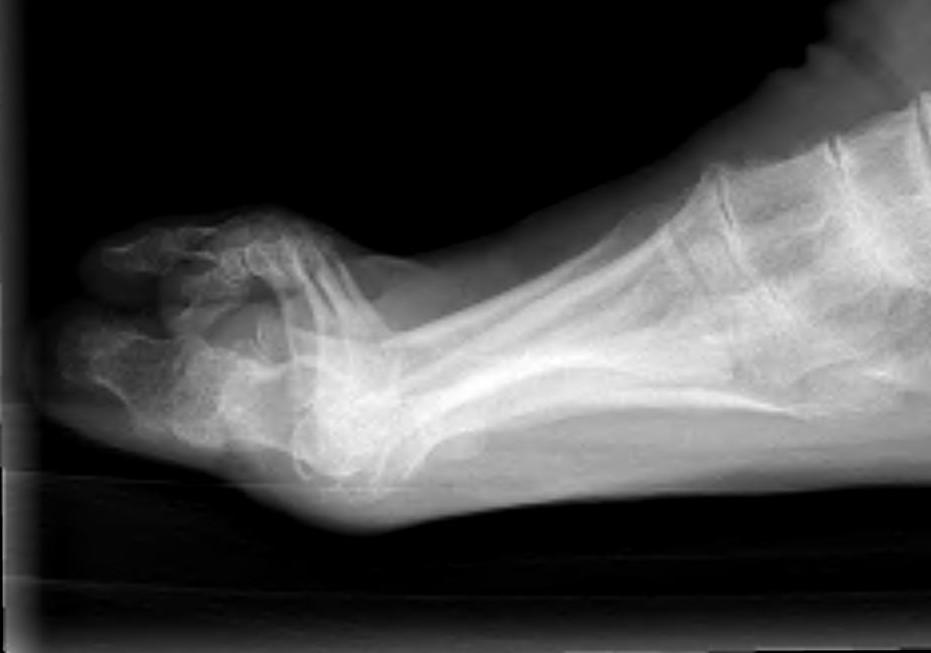

Metatarsalgia

Pathology

Synovitis of MTPJ with capsular destruction

- dorsal subluxation MTPJ

- claw toes develop (MTPJ hyperextended, PIPJ flexed)

- plantar fat pad displaced distally and metatarsal heads exposed to plantar skin

Claw toes

Midfoot

Planovalgus

Causes

- STJ OA / TNJ OA

- tibialis posterior rupture

- synovitis and rupture of the talocalcaneal interosseous ligament